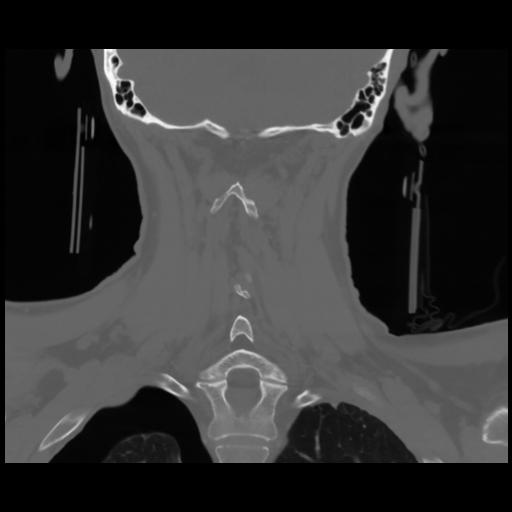

13 P.BLANDAS,,Coronal,2.000,P.BLANDAS,Coronal,